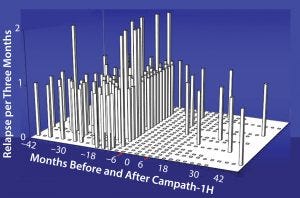

Figure 6: Relapse rate in 22 patients with relapsing-remitting multiple sclerosis; there was a 91% reduction in relapse rate after Campath. Before treatment there were 2.21 relapses/

patient/year. After treatment there were only 10 investigator confirmed episodes, 0.19 relapses/patient/year.

Studies have shown for some time that Campath-1H could be used for treating multiple sclerosis (Figure 6). The treatment has been over a course of only five days, followed by another five-day treatment one year later. During treatment, which depletes lymphocytes and powerfully immunosuppresses patients, the instances of adverse clinical events were greatly reduced. In addition, the patients’ levels of disability seemed to improve (Figure 7). Results from a follow-up study show that clinical improvement was maintained 10 years later.